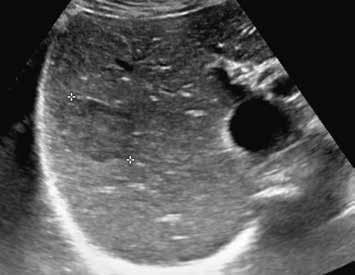

V UZ jsou patrná vícečetná izoechogenní ložiska (1, 2). U jiného pacienta (3) vidíme v játrech převážně hypoechogenní ložiska (žluté šipky) s naznačeným hyperechogenním periferním lemem (červené šipky). Po aplikaci kontrastní látky se ložiska patrná na obr. 1, 2 homogenně sytí a ani téměř po třech minutách nedochází k jejich vymývání (4–6).

V pravém laloku jater jsou na UZ lehce hypoechogenní ložiska s naznačeným výrazně hypoechogenním lemem (1, 2).